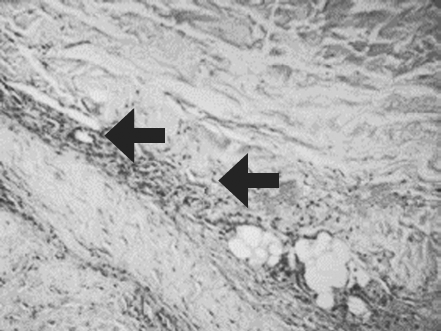

Histological examination of biopsy samples taken from the area of ATMSC transplantation for all the patients revealed the presence of pronounced vascularization with the perifocal proliferation of fibroblasts in both the superficial and deep layers of the dermis (Fig. 6, 7). An immunohistochemical study revealed that the use of ATMSCs resulted in a 5.6-fold increase in the expression of proliferation markers of epithelial and connective tissue cell lines in the injection area (p < 0.01) (proliferation 2.1–2.2), and that apoptotic activity was completely suppressed (Fig. 8, 9). Laser Doppler flowmetry assessment of the microcirculation in the area of stem cell injection on day 7 after early necrectomy, skin grafting, and the administration of MMSCTM showed double the average level of perfusion and mean square deviation of the amplitude of blood flow oscillations than for areas where MMSCTM was not used (p < 0.05) (Table 6).

Fig. 8. Patient D., 34 years old. Significant expression of the proliferation marker of Ki 67 cells of an autologous cutaneous graft on the 5th day after the AMSC injection. Zoom ×600

Рис. 8. Пациент Г., 34 года. Выраженная экспрессия маркера пролиферации Ki-67 клетками аутологичного кожного трансплантата на 5-е сутки после введения мезенхимальных стволовых клеток жировой ткани. Увеличение ×600